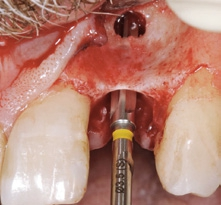

Der chirurgische Eingriff wurde unter Lokalanästhesie mit palatinaler und labialer Infiltration durchgeführt. Zuerst erfolgte die Entfernung des Implantats. Für die Explantation wählten wir das aus unserer Sicht knochenschonendste Verfahren. Mithilfe einer Extraktionszange und mit entsprechend dosierter Kraft drehten wir das teilweise ankylotische Implantat in Achsrichtung aus, um auf jeden Fall die dünne labiale Knochenlamelle zu erhalten (Abb. 3). Dabei frakturierte der osseointegrierte Implantatapex tief im Implantatbett (Abb. 4). Um diesen zu entfernen, musste ein minimalinvasiver apikaler Zugang geschaffen werden. Nach einer krestalen Inzision mit mesialer Tunnelpräparation und distaler Entlastungsinzision sowie der Präparation eines Mukoperiostlappens zeigte sich ein ausgeprägter konkaver Alveolarknochen. Mit einem piezotechnisch unterstützten Chirurgieansatz fenestrierten wir die labiale Knochenlamelle (Abb. 5). Durch diesen minimalinvasiven Zugang lösten wir die ankylotische Verbindung und entfernten den apikalen Implantatrest. Bei dieser Methode der Implantatentfernung wird der periimplantäre krestale Knochen weitestgehend geschont.